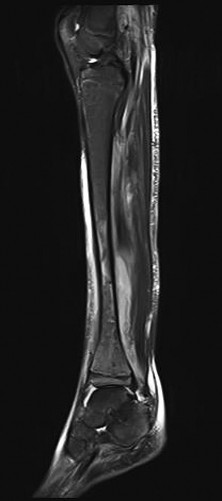

Question 37

An 18-month-old male is evaluated for congenital pseudarthrosis of the tibia (CPT). Examination reveals anterolateral bowing of the affected leg. Which genetic condition is most strongly associated with this finding?